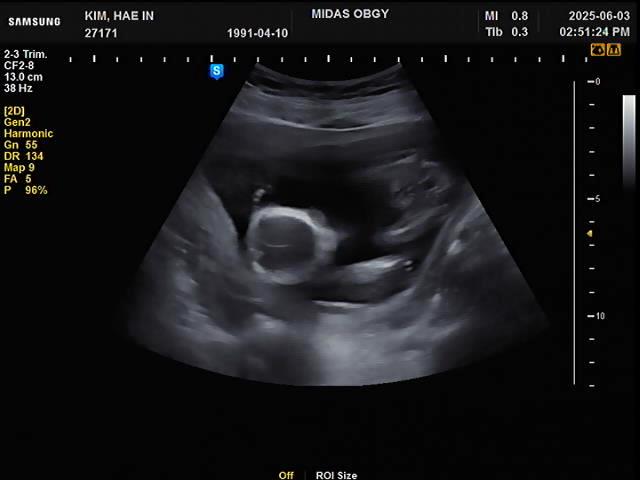

16주차 | 2차 기형아검사 / 성별확인 / 배크기

임신16주차 (25.06.03) 드디어 2차 기형아 검사 초음파로 꼼꼼하게 확인하고 피검사도 하고 1차 검사와 비...